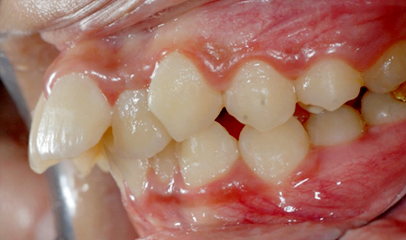

발치 돌출입 교정

전후 사례

발치 교정, 치료기간 약 2년

Before

After